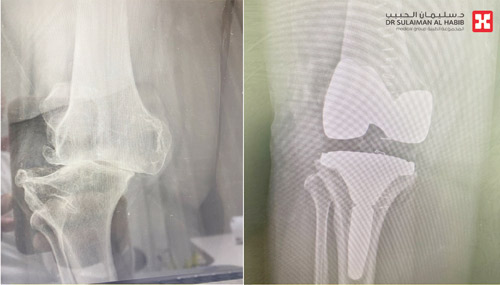

وقال د. الظفيري إن المريضة راجعت المستشفى وهي على كرسي متحرك، وتشتكي من مجموعة أعراض منها عدم القدرة على الحركة والآلام المتزايدة والتورم وتغير شكل مفصل الركبة، بالإضافة إلى ضعف الحركة وصعوبتها. وقد أجريت للمريضة فحوصات أكدت وجود احتكاك من الدرجة الرابعة، مع انحراف في الركبة وارتخاء شديد في أربطتها الجانبية، وخلل في حركة عظمة رأس الركبة. وقام الفريق الطبي بدراسة الحالة على ضوء نتائج الفحوصات بحثاً عن تدخل طبي يناسب الحالة، وخلص إلى إمكانية إجراء عملية لاستبدال المفصل بآخر صناعي يتناسب مع معطيات التشخيص الطبي للحالة. وبعد اتخاذ الترتيبات والتحضيرات اللازمة أجريت العملية مع الاستعانة بأحدث الأجهزة الطبية وتم خلالها استبدال مفصل الركبة بمفصل صناعي يناسب الحالة، وتكللت العملية ولله الحمد بالنجاح، وتمكنت المريضة من المشي على قدميها بعد ساعات من العملية.

وأوضح د. الظفيري أن التقنية التي استخدمت في العملية كانت على نحو مغاير للعمليات التقليدية، ولا تتطلب قطع رباط العضلة الرباعية، وتحافظ على سلامة الكثير من الأنسجة، مما يجنب المرضى الآلام الحادة بعد العملية، كما يجنبهم طول مدتي التنويم والعلاج الطبيعي والتأهيل.